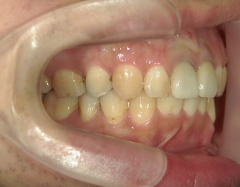

矯正歯科 治療後矯正歯科 全顎ワイヤー矯正 治療後矯正歯科(全顎ワイヤー矯正)治療後

矯正歯科 治療後 E-AMXというセラミックにて左右上1番を被せ直しました。

no.24_8228_治療後_右.jpgno.24_8228_治療後_正面.jpgno.24_8228_治療後_左.jpg